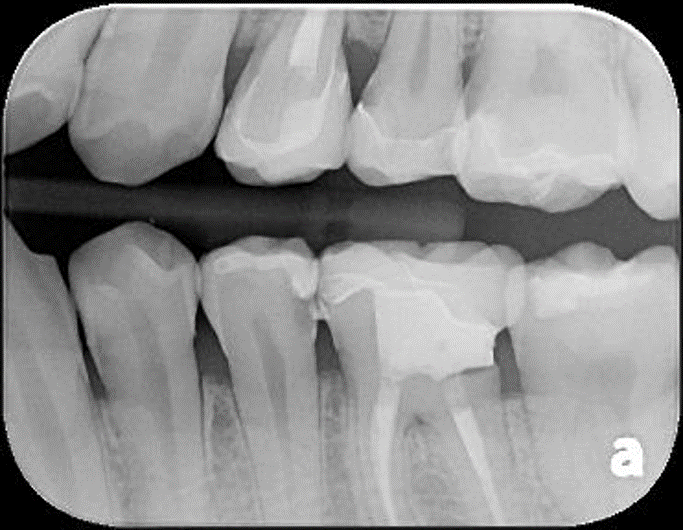

二次蛀牙,牙髓未受侵犯

根尖片顯示邊緣密接良好